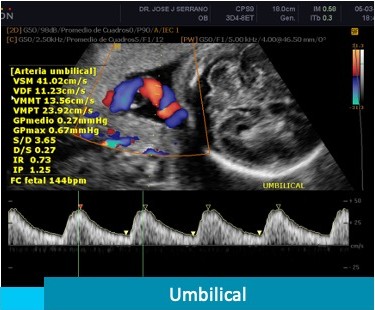

La ecografía Doppler es un complemento de la ecografía del tercer trimestre, en la cuál se estudian y analizan; mediante color y sonido, el flujo de los vasos sanguíneos del bebé. Este estudio nos permite valorar el estado de salud y bienestar del feto.